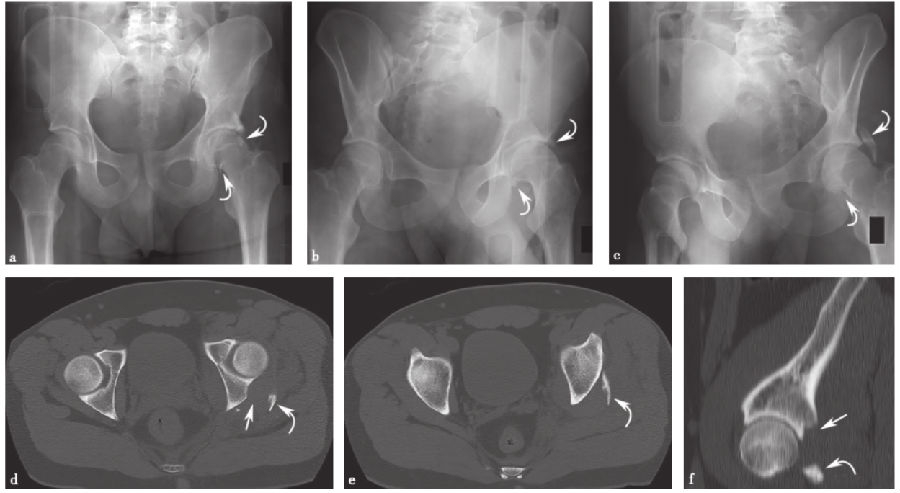

5、孤立后壁髋臼骨折:

孤立后壁髋臼骨折(图14)是髋臼骨折最常见的类型之一,发生率为27%。因此,髂坐线完整时,不考虑横行后壁骨折的分型。然而,髂坐线的破坏可能会或不会作为粉碎后壁组分的延伸存在。斜Judet位X线片和CT有助于显示孤立后壁髋臼骨折。

图14 孤立后壁髋臼骨折a.骨盆正位X线片;b、c.双侧斜位骨盆X线片;d、e.轴向CT扫描;f.矢状面CT重建。直线箭头示骨折部位,弯曲的箭头示后壁骨折块。